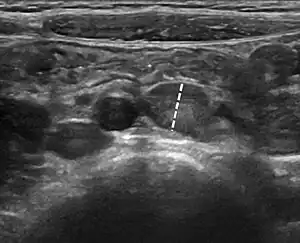

| Abdominal ultrasound showing large mesenteric lymph nodes in a 6-year-old with mesenteric lymphadenitis. The largest lymph node (dashed line) measurement was 9 mm.[1] | |